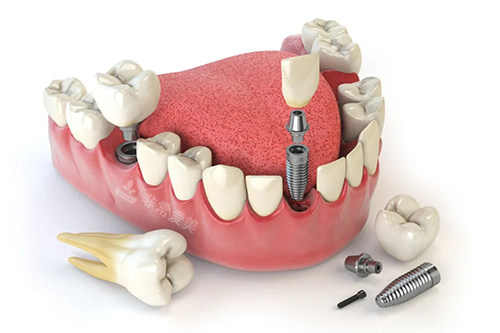

牙齿种植卡通示意图

问:乐美口腔种牙技术如何体现优势呢?

答:乐美口腔的种牙技术优势明显。

一方面,他们引进了国内外比较靠前的种植系统,这些种植体具有良好的生物相容性和稳定性,能够与牙槽骨紧密结合,大大提高了种植牙的成功几率。

另一方面,乐美口腔的医师团队在种植牙领域有着深厚的造诣,他们会在术前为患者进行齐全的口腔检查和评估,制定科学合理的种植方案。

在种植过程中,凭借优质的技术和丰富的经验,确保种植手术的更准一些性和靠谱性。

术后,还会对患者进行长期的跟踪和维护,让患者能够放心地使用种植牙。